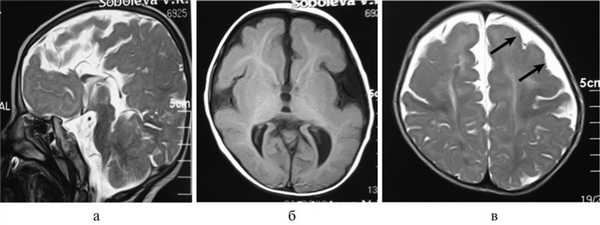

Рис. 2. Результаты обследования больной С., 8 лет. а, б, в — МРТ головного мозга (сагиттальная и аксиальная проекции): сочетание АМТ и диффузной пахигирии (стрелки).

Важной находкой при АМТ на МРТ является параллельная ориентация тел боковых желудочков по отношению друг к другу (рис. 4, а), расширенные фронтальные отделы желудочков, так называемый «симптом ухвата».

Рис. 4. МРТ головного мозга больной К., 4 года. АМТ. Аксиальная проекция: а — аномальная параллельная ориентация тел боковых желудочков по отношению друг к другу (стрелка); б — фронтальное сечение: деформация передних и задних рогов боковых желудочков, своеобразный U-образный характер фронтальных отделов боковых желудочков (стрелка).